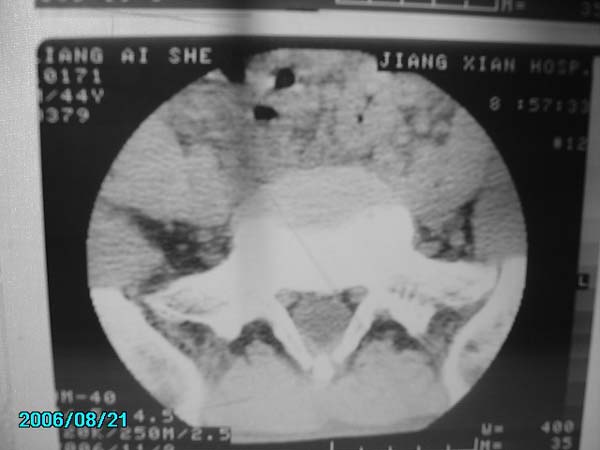

男,40岁,腰疼半年

腰4-5椎间盘后缘变平直,可考虑椎间盘轻度突出。余未见异常。

l4/5椎间盘膨出。

腰4-5椎间盘轻度突出。余未见异常。

l5-s1右侧后突出

腰椎侧弯,l4-5椎间盘膨出。

我还看见了指纹

腰4-5、腰5-骶1椎间盘后缘变平直,可考虑椎间盘轻度突出。余未见异常

除有第3-5腰椎椎体后缘中央血管沟显示外,诸椎间盘比较正常。我也象13081830109战友那样看见了指纹,呵呵。